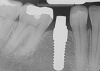

Fig 17. 12-week postoperative radiograph.

Figure 17

The final impression appointment follows the light-load phase, provided the implant is stable and the soft tissue is acceptable to the clinician. Polyvinyl putty and light-body impression materials were used in this case; analog casts and final full-zirconia full crowns were fabricated (Figure 16). The patient provided feedback that chewing was comfortable and without food impactions. Keratinized gingival cuff was developed, and natural-tooth contours for the restorations mimicked what is normally found in human dentition. The healed bone surrounding the ceramic dental implant was similar in density and crestal levels in comparison with the adjacent natural teeth, evident in the radiographic evaluation (Figure 17). Final long-term restorations at the gingival crest and restoration interfaces were also consistent in optimum periodontal health and gingival height. Arch-form integrity was upheld and occlusion was managed; osseointegration and light-load principles optimized the success of the restorations, and an acceptable, harmonious esthetic outcome was achieved for the patient.